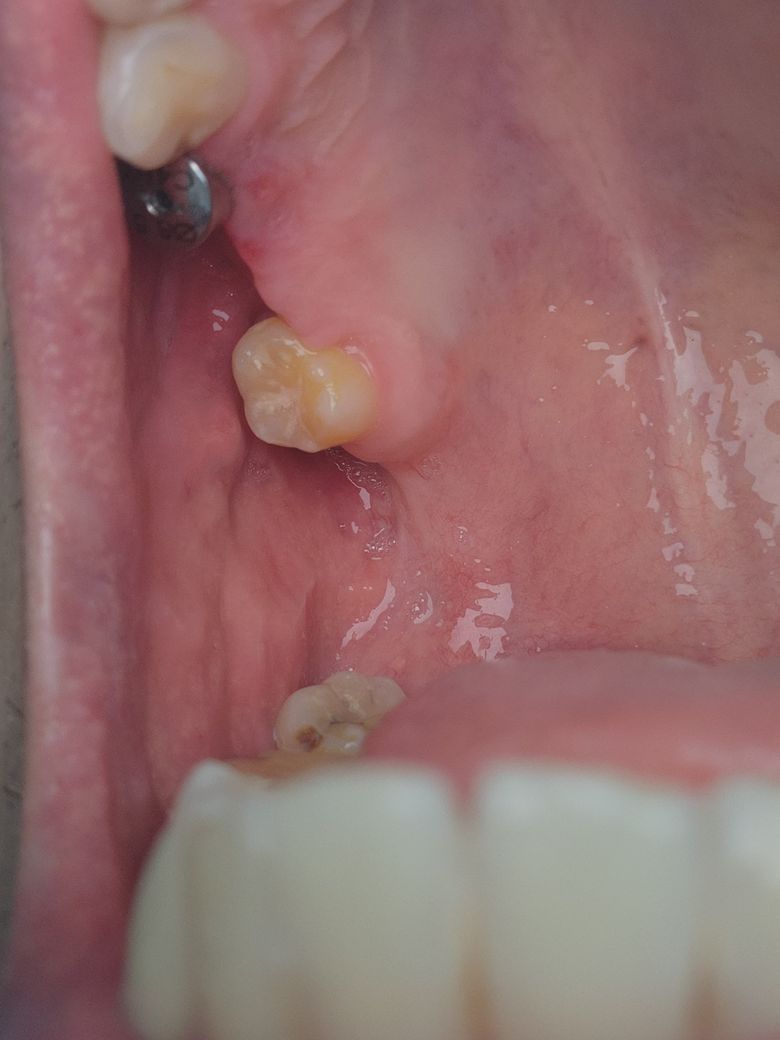

구내염 일까요~? 임플란트 염증 일까요~?

8월7일 이번주 월요일부터 잇몸 부위가 따가웠는데

양치질을 쎄게했나 싶어 지켜보았습니다.

금요일이 될때까지 따가운데

의사선생님이 보시기에는

구내염 일까요~? 임플란트 염증 일까요?

현재 사진상으로는 임플란트 염증일 가능성도 있기에 통증이 지속되는 경우 치과를 방문하여 진료를 받길 권합니다.

구내염이나 임플란트 염증은 아닌거 같습니다. 그냥 잇몸에 상처가 좀 난거 같으니 너무 걱정하지 않으셔도 될것같습니다.

잇몸에 상처가 있는듯 보입니다.

해당부위로 음식이 자극되거나 하지는 않았는지 확인해보는것이 좋습니다.

손상된 잇몸은 보통 2주정도 지나면 회복됩니다.

그이후에도 염증이 줄어들지 않는다면 치과에서 진료를 받는것이 좋습니다 .

임플란트 염증이면 붓고 피가나는 등의 증상이 나타납니다. 사진상으론 구내염으로 보입니다.